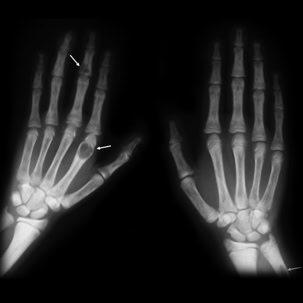

X-ray image of two human hands showing bone structure, with arrows pointing to areas of abnormality or lesions on the left hand.

Las fracturas óseas nunca se producen en el húmero, pero, por desgracia, son bastante frecuentes, sobre todo cuando se trata de dos lesiones en el trabajo. Como abogado de compensación de trabajadores que sirve Atlanta, muchos casos vienen a través de mi puerta que implican fracturas. Hoy quiero repasar algunos detalles sobre las fracturas óseas: